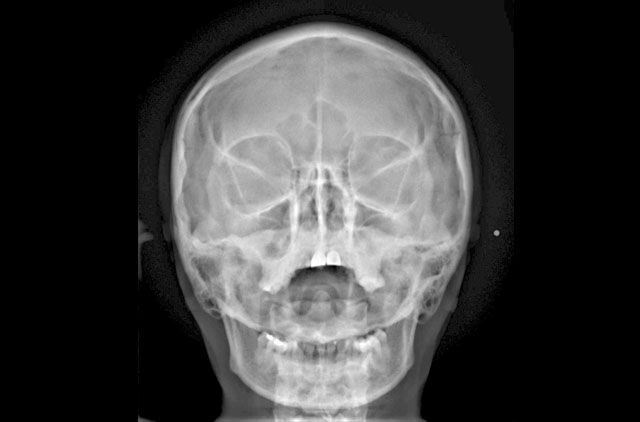

-Anteroposterior (AP)

-Posteroanterior (PA)

-Caldwell

Radiografía Senos Maxilares y Paranasales

-Senos Maxilares Dos Proyecciones

-Senos Paranasales

-Senos Paranasales 3 Proyecciones (Caldwell, Waters, Senos p.)